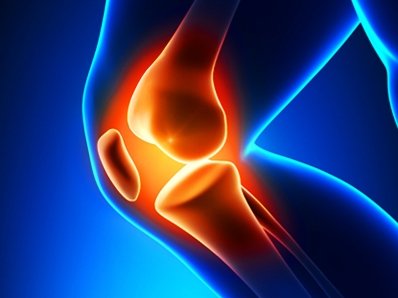

دکتر جمشید جهانی، مسئول کمیته تحقیقات و پژوهش هیات پزشکی ورزشی استان فارس، ضمن بیان مطلب فوق افزود:محافظت از زانو در سنین جوانی میتواند از بروز مشکلات جدیتر مانند آرتروز و مشکلات زانو در سنین بالا پیشگیری کند. هر زمان که شما قدم برمیدارید سه برابر وزن خود را به زانوی خود وارد میکنید. زمانی که میدوید فشار وارده به ۵ برابر میرسد. زمانی که میپرید شدت فشار ۷ برابر میرسد. اگر مرتبا در زانوهای خود احساس درد میکنید، تغییر شیوه زندگی میتواند به عنوان اولین اقدام مورد نظر قرار بگیرد.

وی افزود:کاهش وزن تا ۷۰ درصد و ورزش کردن تا ۳۰ درصد میتواند در کاهش دردها موثر باشد. ورزشهای با شدت متوسط مانند شنا و دوچرخه سواری نیز بسیار بهتر از دویدن یا شنا کردن میتواند در حفاظت از زانوها موثر باشد. تقویت عضلات رانها و کمر در کاهش فشار زیاد روی زانوها موثر است.

دکتر جهانی گفت:اگر بیش از دو هفته به طور مداوم احساس زانودرد دارید حتما باید به پزشک مراجعه کنید، چرا که ممکن است مشکلی در زانوی شما وجود داشته باشد که با گذشت زمان امکان حادتر شدن آن وجود دارد.